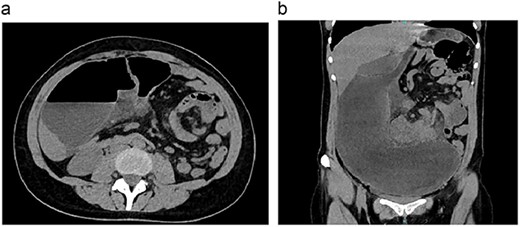

On clinical evaluation, a dehydrated patient with severe abdominal pain with tenderness was encountered; her vitals were normal, but a 5 x 5 cm non-painful mobile mass was detected on her upper abdomen. No other masses or lymph nodes were seen at that time. Due to this, abdominal computed tomography (CT) was requested, revealing dilated small bowel loops >6 cm with thickened wall, whirl sign and a small amount of free liquid in her abdomen (Fig. 1A and B).

(a) CT, showing bowel loops distended. (b) CT, the volvulus of the small bowel is seen.